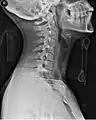

A side view of a person wearing a C spine collar.